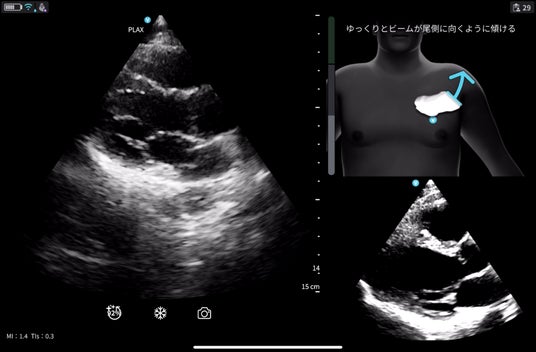

※Cardiac Guidance/ Interpretationの実際の画面

リアルタイムで操作者をサポートするガイド機能で、プローブ(探触子)の位置、角度、肋間操作、深度を画面上で指示し、より正確で高品質な画像取得をサポートします。さらに、画像品質のインジケータ機能を備えており、最適なスキャン画像が得られているか否かを判定します。また、一定レベル以上の品質を認識した際には、プローブを一定時間保持することで自動的に画像を保存します。Cardiac Guidanceの機能により、複雑な心エコー検査を簡便かつ正確に実施することが可能となり、臨床現場だけでなく、大学や基幹病院のトレーニングセンターでの教育利用にも「Vscan Air SL Ally」の導入が期待されます。

※Cardiac Guidanceによる心エコー検査のリアルタイムガイド表示機能。Quality Meterで画像クオリティを確認、画面上部にはイラストとともに「時計回りにゆっくりと回転」などリアルタイムに様々なガイダンスが表示されます。